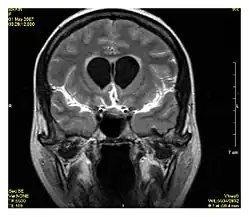

| Fluid-attenuated inversion recovery | FLAIR | Fluid suppression by setting an inversion time that nulls fluids | High signal in lacunar infarction, multiple sclerosis (MS) plaques, subarachnoid haemorrhage and meningitis (pictured).[15] |

Inversion recovery is an MRI sequence that provides high contrast between tissue and lesion. It can be used to provide high T1 weighted image, high T2 weighted image, and to suppress the signals from fat, blood, or cerebrospinal fluid (CSF).[40]